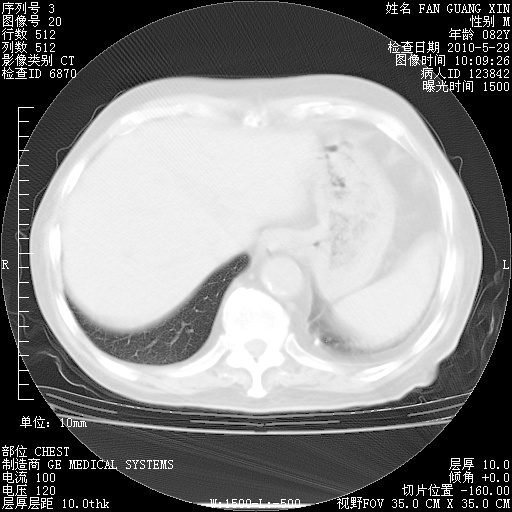

再治疗10天后的肺部CT

再治疗10天后的肺部CT 纵膈窗

从白细胞总数和中性比例看好像合并感染。肺部纹理好像比上次多,支气管炎?其他感染?

阅读此次胸部CT,肺间质渗出性改变较入院时有吸收。目前从体温、白细胞、中性分叶明显增高,肯定存在细菌感染(发生医院感染哦,若无消化道及泌尿系统等感染的依据,肺部感染可能大)。若你院头孢哌酮舒巴坦钠耐药率较高,同意你的方案,若48小时体温仍高,可考虑使用碳青霉稀类抗菌药物,同时可予超声雾化、注意滴数时加大液体量。白蛋白33.30g/L较低哦,需加强营养等支持治疗。